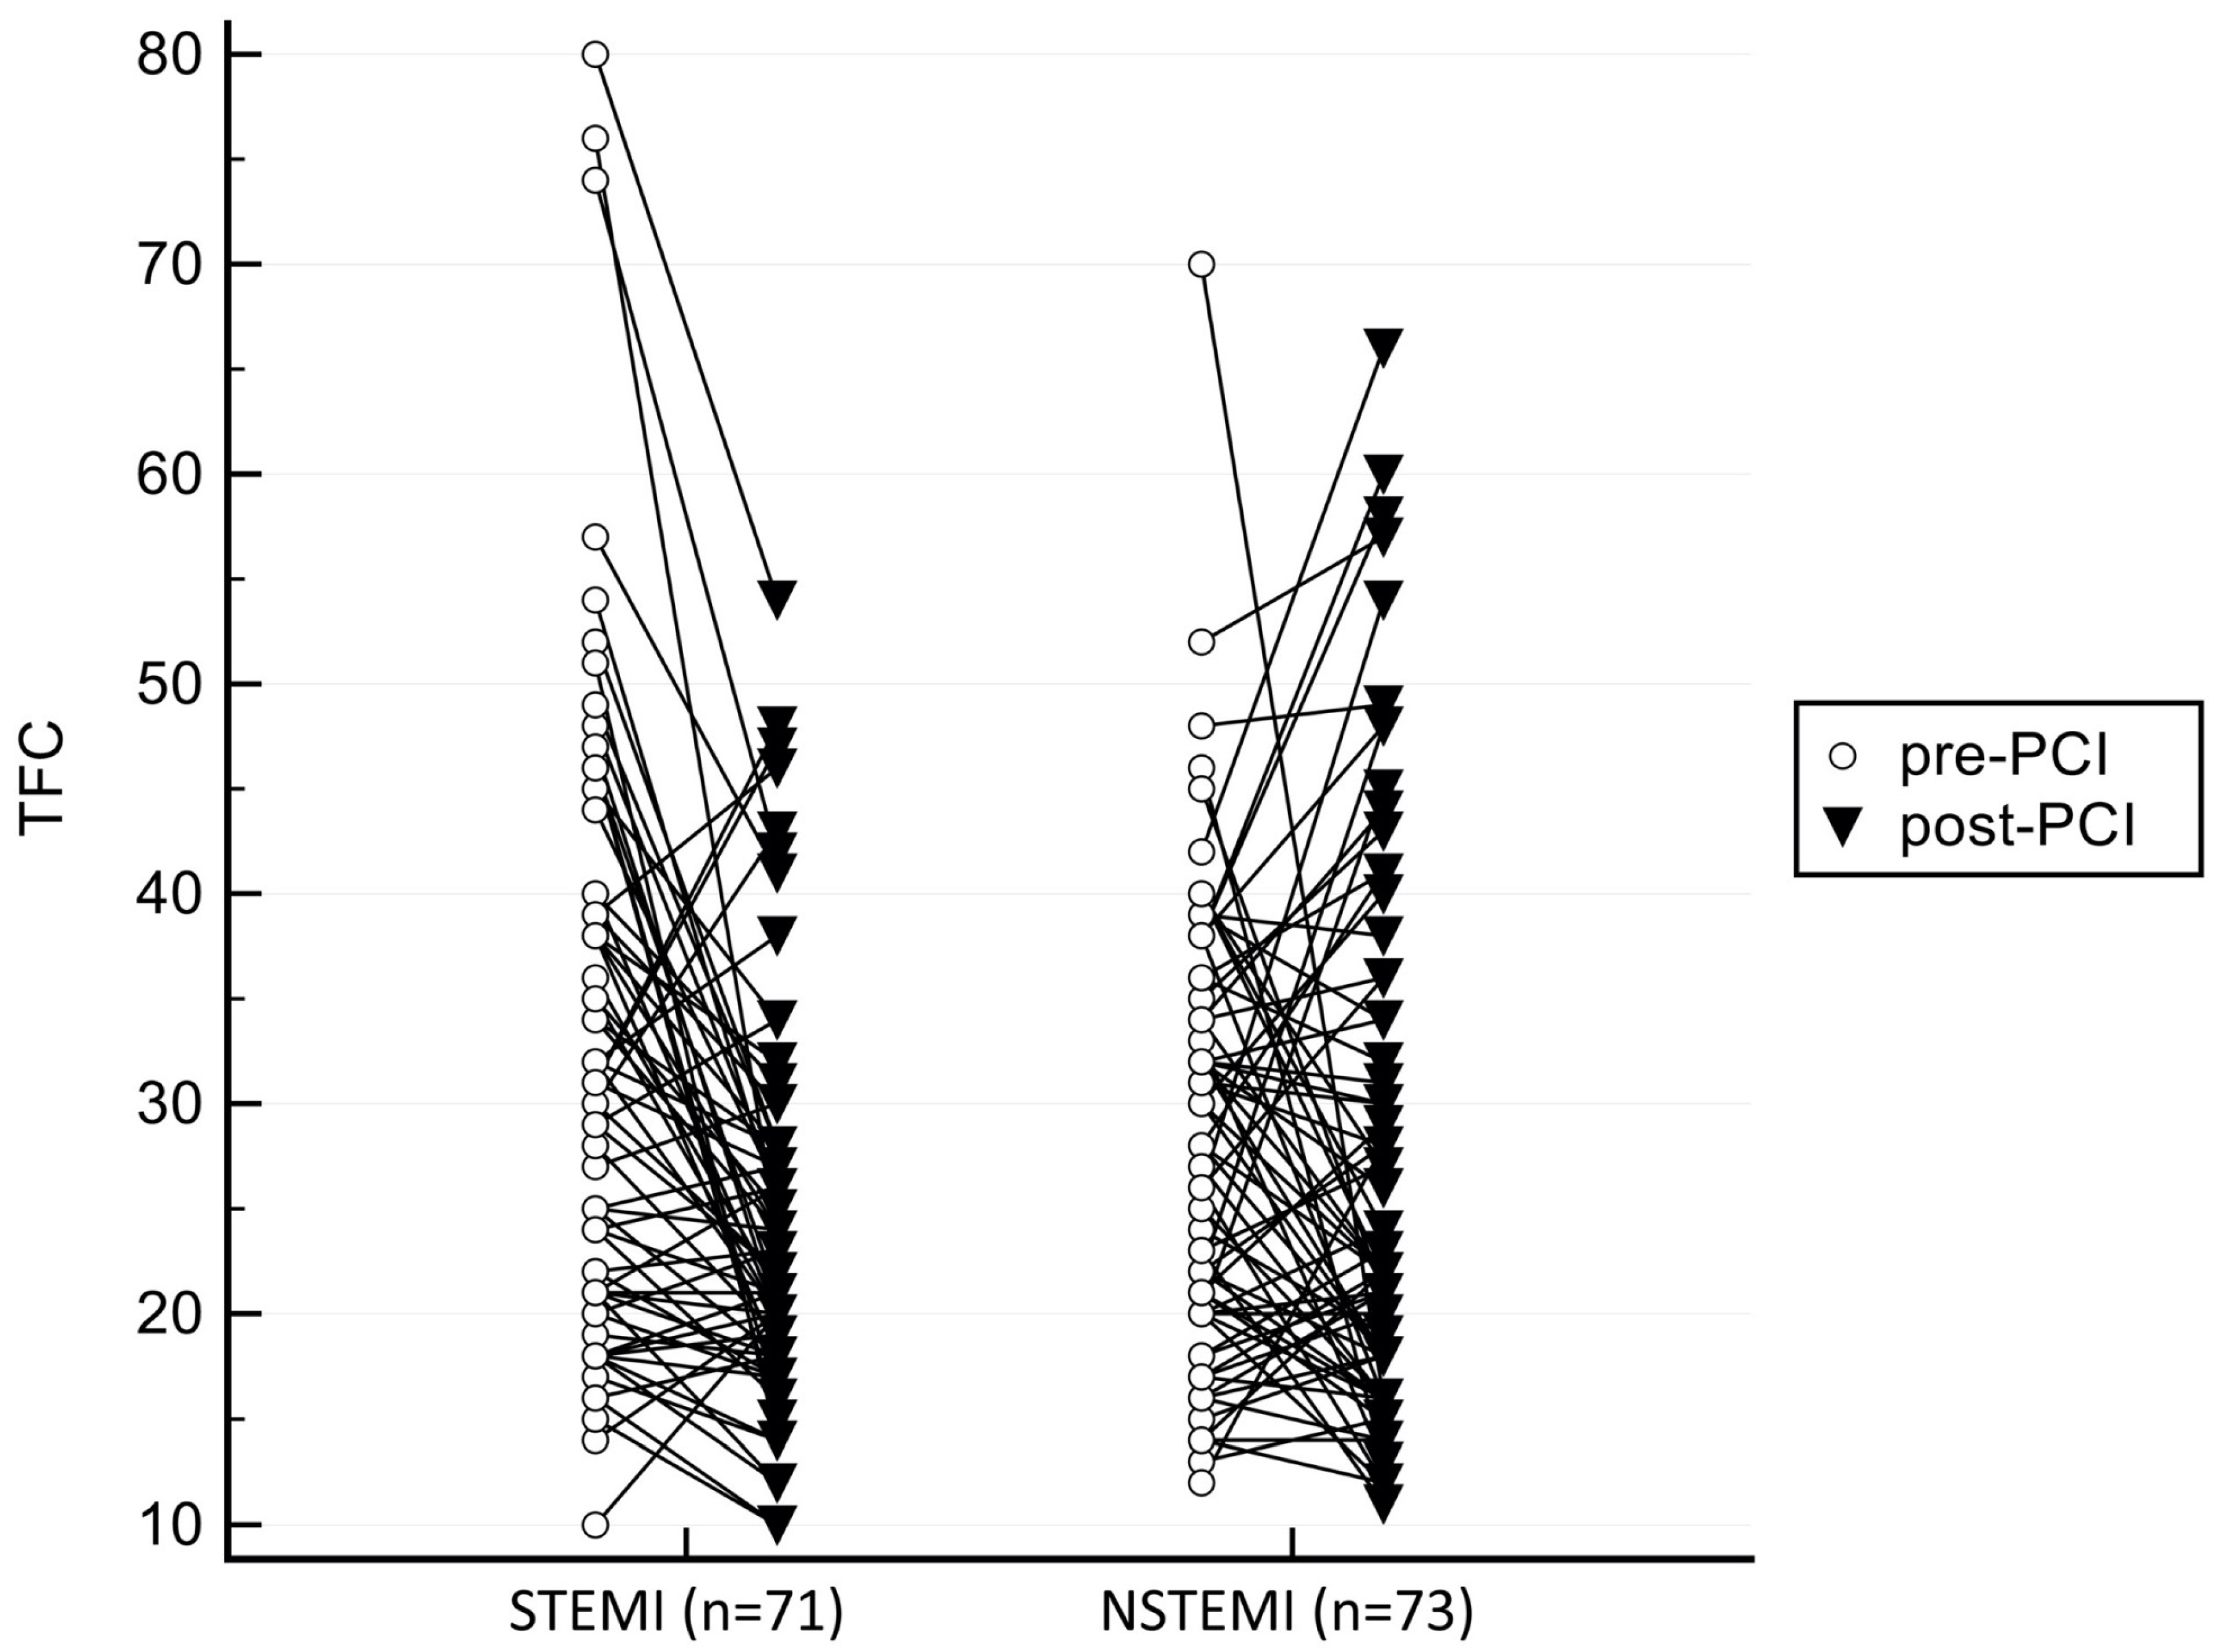

| TFC pre-PCI | 32.42 ± 14.49 | 28.34 ± 10.57 | 0.056 |

| TFC post-PCI | 24.37 ± 9.21 | 26.89 ± 13.16 | 0.184 |

| Significance of ΔTFC | p < 0.001 | p = 0.324 |